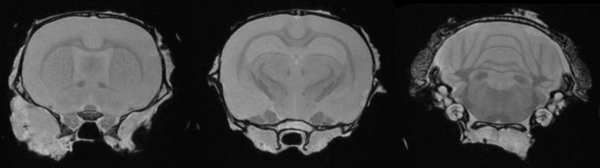

Epilepsy in the rat brain: T2- weighted images of a rat brain 48 hours after induction of epilepsy.

Epilepsy in the rat brain: T2- weighted images of a rat brain 48 hours after induction of epilepsy. Image Credit: Scintica Instrumentation Inc

T2- weighted images of a rat brain 48 hours after induction of epilepsy.

T2- weighted images of a rat brain 48 hours after induction of epilepsy. Image Credit: Scintica Instrumentation Inc